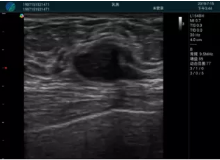

可視化甲狀腺穿刺引導(dǎo)

頸動脈血流充盈飽滿,無外溢

肝內(nèi)血管顯示清晰,血流敏感無外溢

病例二:

甲狀腺囊性結(jié)節(jié),囊壁鈣化,透聲好

甲狀腺囊性占位

2001年美國健康護理研究和質(zhì)量監(jiān)督局(AHRQ)批準了一項關(guān)于提高患者安全性的報告,建議:在頸內(nèi)靜脈中心置管術(shù)時使用超聲引導(dǎo)。此后超聲引導(dǎo)穿刺被用于幾乎所有的急診穿刺操作,尤其是血管穿刺。

便攜超聲在急診穿刺中的應(yīng)用:

* 提高了穿刺成功率

* 減少了穿刺損傷及并發(fā)癥

* 縮短了操作時間

* 減輕了患者痛苦